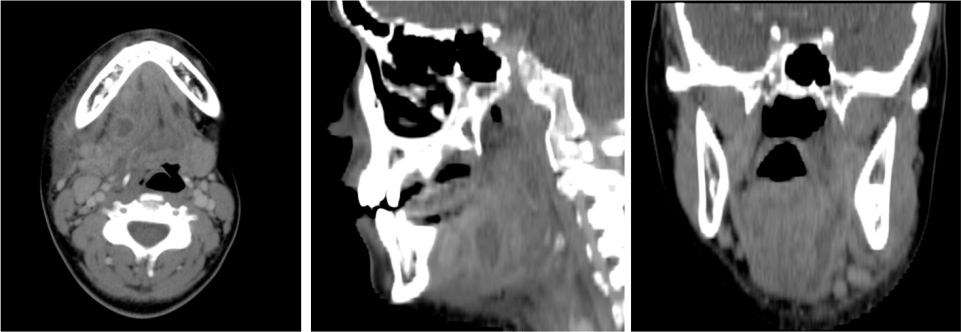

La TC multicorte con contraste intravenoso es la técnica de elección debido a la rapidez y accesibilidad de la prueba.

Protocolo estándar:

- Desde borde superior del peñasco y el borde superior del manubrio esternal

- Paciente en decúbito supino con los brazo extendidos a ambos lados del cuerpo. Mandíbula extendida.

- CIV: 80 ml / 3ml x seg. Retraso de 50 segundos.

- Postprocesado de imágenes: reconstrucciones MPR coronales y axiales con ventana de partes blandas y hueso, con un grosor de corte de 2-3 mm.

Es importante recordarle al paciente la necesidad de realizar movimientos respiratorios suaves y no deglutir durante el tiempo de adquisicón de las imágenes, para evitar al máximo artefactos de movimiento derivados de estas acciones.

Amigdalitis, Absceso periamigdalino y parafaríngeo:

La clínica no permite diferenciar con exactitud entre celulitis y absceso y no permite determinar con exactitud la extensión del proceso. Clínicamente se sospecha un absceso cuando existe dolor en región cervical y amígdalas que empeora progresivamente a pesar de antibióticoterapia oral, fiebre persistente, odinofagia, voz gangosa, adenopatías cervicales dolorosas y en algunas ocasiones trismus.

Hallazgos:

- Aumento de tamaño de las amigdalas (amigdalas «besándose») con aumento de realce tras tras aplicación de contraste iv.

- En fases avanzadas surgen hipodensidades parenquimatosas o colecciones líquidas debido al edema y la celulitis existente.

- Un absceso periamigalino se diferencia de la celulitis porque presenta una licuefacción/colección central con anillo periférico realzado que puede o no presentar burbujas de aire en su interior. Un absceso de morfología irregular indica estadio más evolucionado.

- El absceso puede extenderse al espacio parafaringeo, constituye el 9% de todas las masas parafaríngeas.

- La distinción entre celulitis y absceso es importante en lo que al tratamiento se refiere. Si existe una colección drenable, la aspiración es el tratamiento requerido. Una colección con anillo periférico realzado, es compatible con absceso drenable en el 63-77% de los casos, población pediátrica y adulta incluida.

- Puede observarse agrandamiento y realce de la úvula.

- Es frecuente identificar adenopatías cervicales.

- Es frecuente observar una mala delimitación de los tejidos blandos adyacentes y las adenopatías cervicales.

- Una vez que la infección ha remitido, pueden quedar calcificaciones residuales en la amígdala.